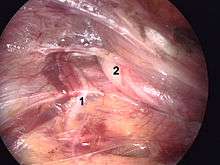

Laparoscopic repair

There are mainly two methods of laparoscopic repair: transabdominal preperitoneal (TAPP) and totally extra-peritoneal (TEP) repair. When performed by a surgeon experienced in hernia repair, laparoscopic repair causes fewer complications than Lichtenstein, particularly less chronic pain. However, if the surgeon is experienced in general laparoscopic surgery but not in the specific subject of laparoscopic hernia surgery, laparoscopic repair is not advised as it causes more recurrence risk than Lichtenstein while also presenting risks of serious complications, as organ injury. Indeed, the TAPP approach needs to go through the abdomen. All that said, many surgeons are moving to laparoscopic methodologies as they cause smaller incisions, resulting in less bleeding, less infection, faster recovery, reduced hospitalization, and reduced chronic pain.[11][12]